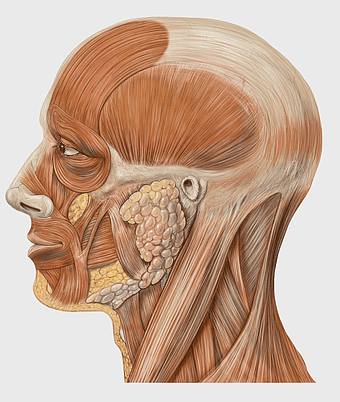

human head anatomy diagram, facial muscles illustration, parotid gland structure, cranial nerves visualization, head and neck dissected anatomy, detailed face muscle map, skull and organ depiction -